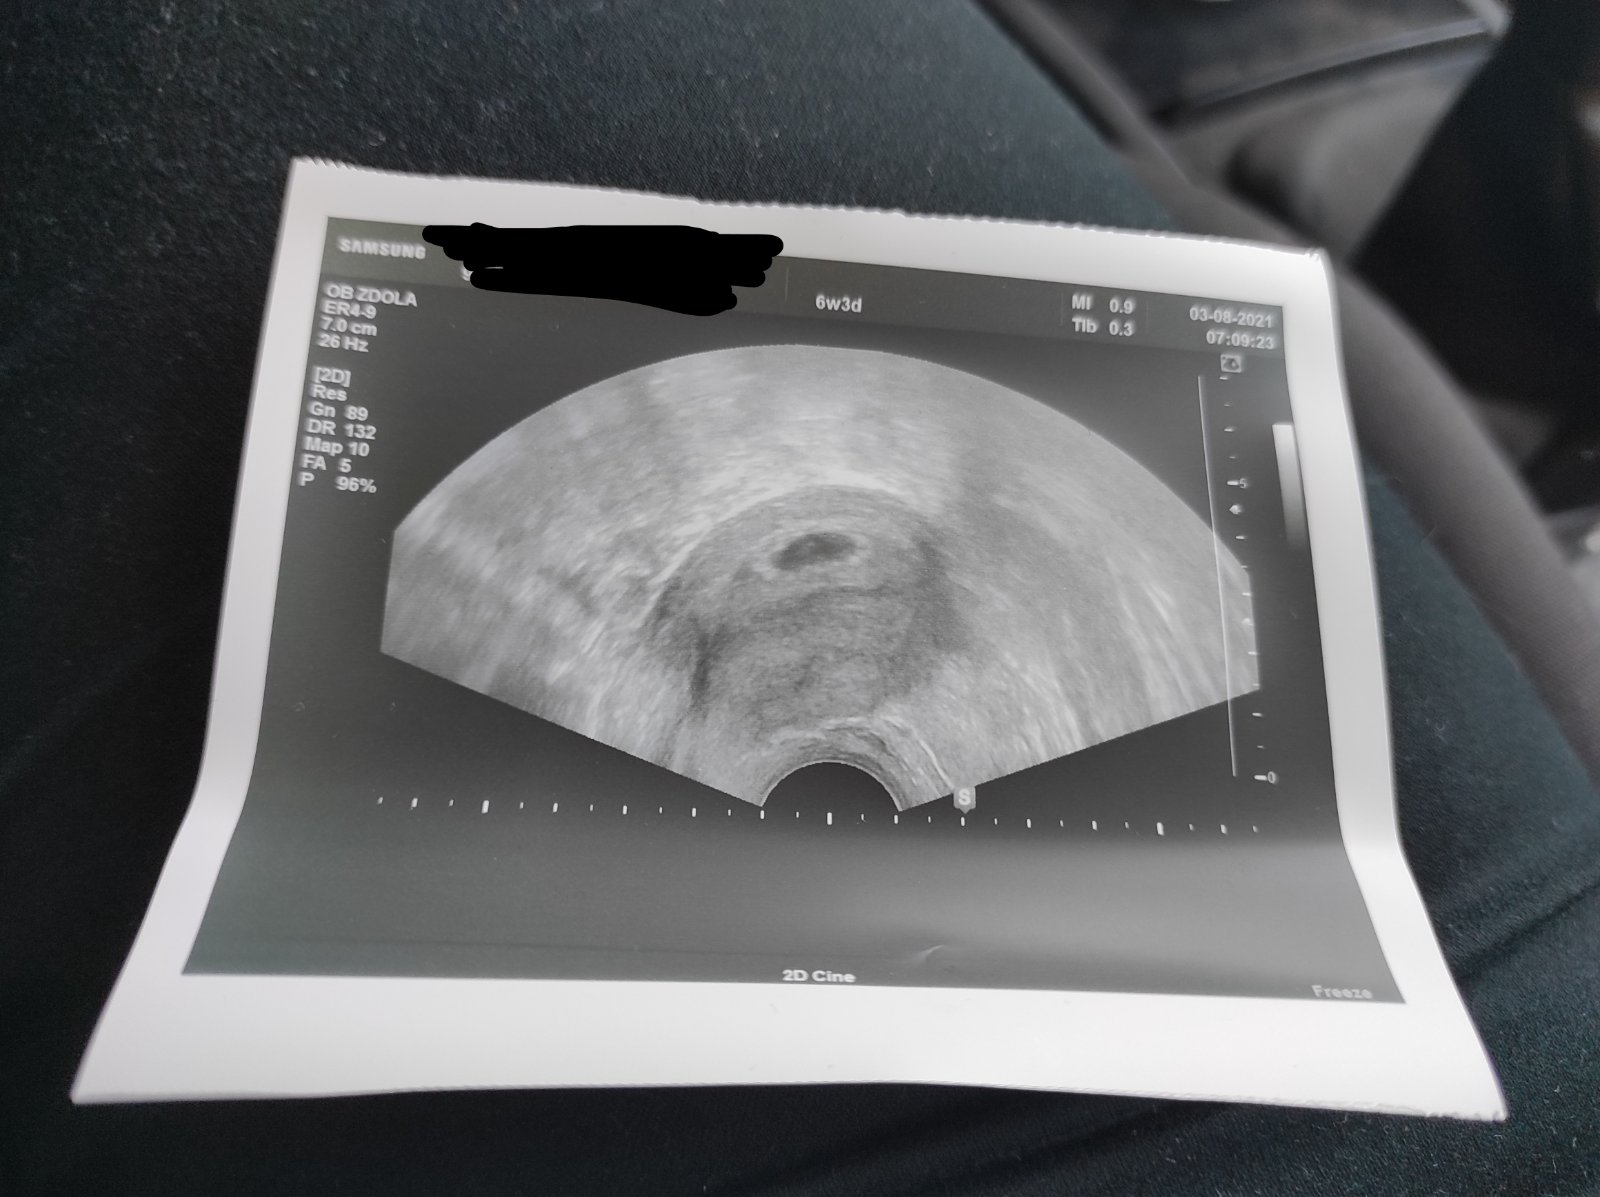

@veverka_25 Tak jdeme z gyndy, těhotenství pptvrzeno, hcg 676 ale na UTZ viděl jen mini tečku.

Za 3 týdny kontrola, odběry, UTZ a snad bude srdíčko 😊

Lékař sám nevěděl kolik přesně jsem, protože bych měla dle MS být 6+4... Dle UTZ o týden méně ale nejspíš i proto že jsou tam zatím gestační váčky dva, ikdyž jeden menší... Uvidíme příští týden, zda budou obě prosperující 😊😊 ale aspoň vím, proč mám HCG vyšší než odpovídající týdnům těhotenství 😂😂😂